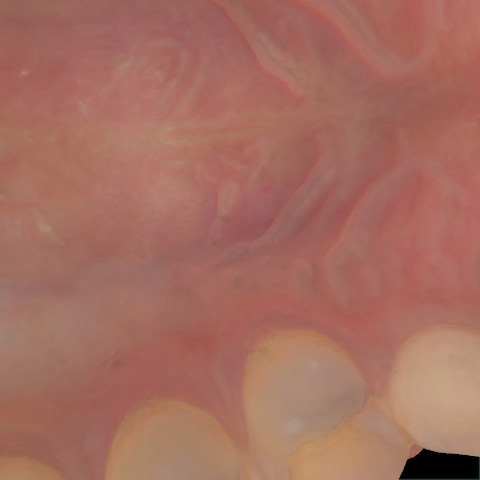

Image 93 / 121

NHD30676

Annotated as "Good"